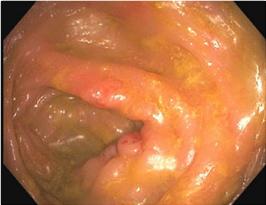

食管胃十二指肠镜和结肠镜检查显示除盲肠外的整体外观正常,盲肠显示结肠炎,其内腔狭窄且标志扭曲,妨碍回盲瓣插管(图2)。病理学报告显示无明显组织病理学变化。然而,考虑到临床表现、影像学和实验室检查,累及回肠末端的克罗恩病被认为是最有可能的诊断。

图2、水肿盲肠的图像